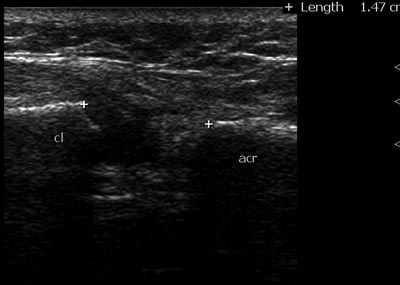

Есть ли показания для оперативного вмешательства у женщины с застарелым разрывом АКС? Женщина обратилась с жалобами на боль в области плечевого сустава на протяжении 4,5 месяцев после травмы. Боль беспокоит при подъеме руки от 45 град до 90. Также беспокоит онемение 3- 4 пальца кисти, периодически возникающий отек кисти. В сентябре после травмы диагностирован разрыв АКС слева Tossy 1, была наложена повязка Дезо. Затем периодически получала разные виды физиотерапии, мази без эффекта.Был проведен повторный Rg. На УЗИ я выявила расширение АКС до 15 мм, (на здоровой стороне суставная щель до 5 мм), содержимое неоднородное, имеется неровность дистального конца ключицы. Признаки разрыва акромиально-ключичной связки. Целостность сухожилий ротаторной манжетки сохранена. Выпота в сумках нет.Описание Рентгенолога: 1ый снимок октябрьский , второй справа -середина февраля (недавно). 1 ый снимок сделан с грузом - второй - без груза. На рентгенограмме левой плечевой кости с плечевым суставом с центрацией на левый АКС от февраля года в сравнении с рентгенограммой от октября отмечается разрыв КАС первой степени по Tossy, в динамике расстояние левого КАС с 0,7 мм и ступенеобразной деформацией увеличилась до 1,1 см (я не опечаталась - такова размерность в заключении) с признаками лизирования эпифиза левой ключицы, реакция мягкотканного компонента отсутствует.Подскажите, пожалуйста, какая же здесь степень разрыва по Tossy? Необходимо ли оперативное вмешательство, по поводу данного разрыва? Считаете ли Вы, что есть разрыв связки? Какова дальнейшая тактика ведения пациентки.